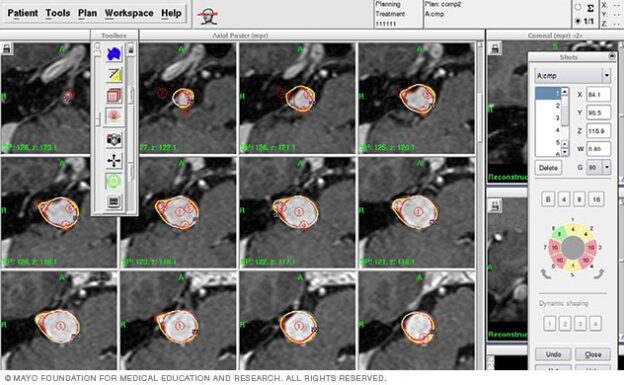

3. Imaging & Targeting Protocols

High-resolution MRI with thin slices, contrast sequences, and fused CT angiography (for AVMs) provide the accurate structural and vascular maps required for contouring. For AVMs, digital subtraction angiography (DSA) remains the gold standard in many cases and is integrated into planning when needed. Institutional imaging protocols align with those used in major multicenter studies to allow comparable dosimetric decisions and outcome tracking.

4. Dose, Volume, and Fractionation Decisions

Radiation dose and fractionation are chosen based on lesion size, proximity to critical structures (brainstem, cranial nerves), and published volumetric outcome data. For example, smaller skull base meningiomas may be treated with a single-fraction high-dose SRS regimen if critical distances permit; where nerves or brainstem proximity is close, hypofractionated SRS (fractionated stereotactic radiotherapy) may be selected to decrease cranial neuropathy risk — an approach supported by multicenter experience.